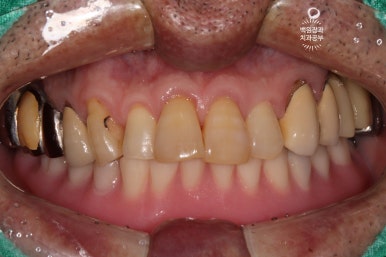

드디어 전체임플란트가 완성되었습니다!!

짜잔!!! 정말 비슷한 색상으로 제작이 잘 되어왔습니다.

최종 크라운을 연결하고나니 그렇게 깔끔할수가 없네요.

정면 사진입니다.

무면허업자에게 치료 받으셨던 어금니는 이제 하얀 지르코니아 크라운을 가진 임플란트로 대체되었습니다.

아래 틀니는 사라지고, 이젠 고정식의 임플란트로 바뀌었네요!

작은 충치들은 치아색의 레진으로 치료되어, 최종 치료결과는 아주 만족스러움 그 잡채!